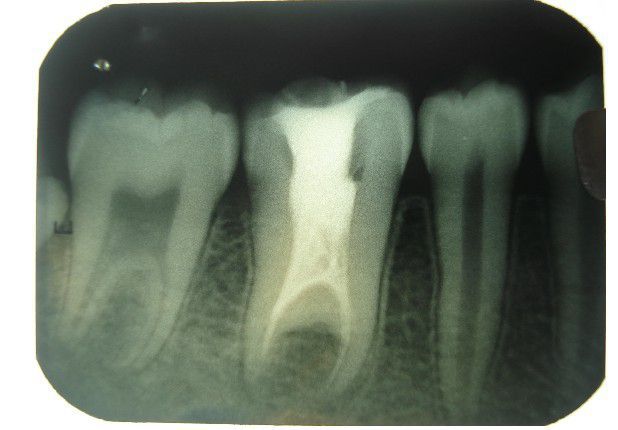

Taurodontism is a developmental disturbance of a tooth in which body is enlarged at the expense of the roots. An enlarged pulp chamber, apical displacement of the pulpal floor and lack of constriction at the cementoenamel junction are the characteristic features. It appears most frequently as an isolated anomaly